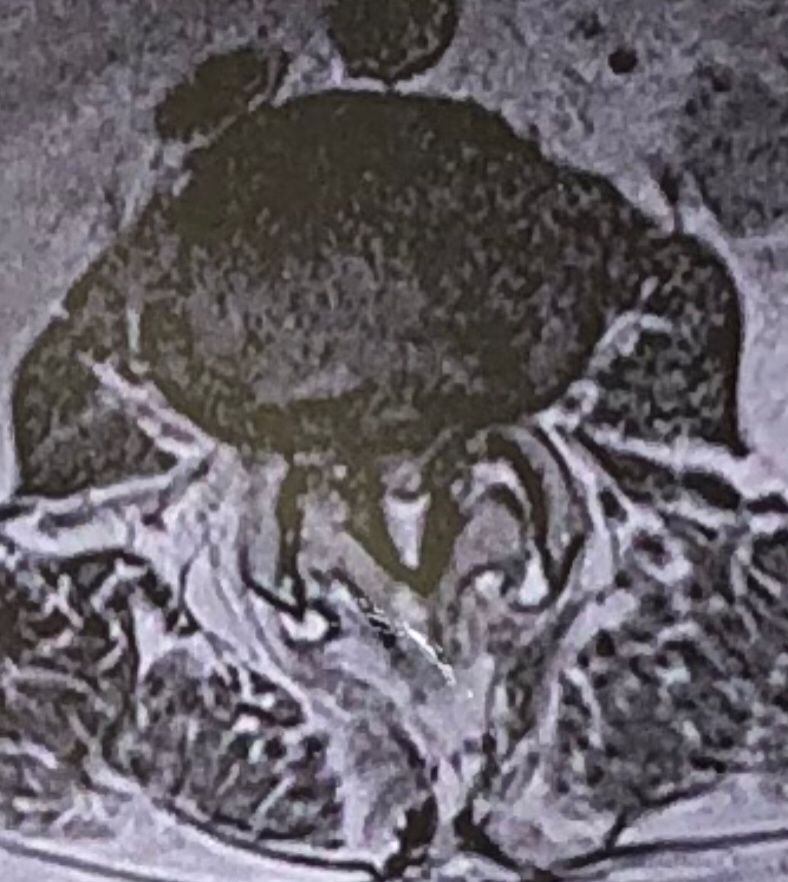

70 yrs old female presented to my clinic today (Oct 06/2024)due to severe LBP with both legs pain for several years.

7 years ago came to my clinic with L leg radicular pain and I referred her to a neurosurgeon. Patient underwent full laminectomy from L1 to S1. Few months after surgery her LBP and legs pain were started and hasn’t improved since then. Now walking aggravates the pain and forces her to bend forward. Patient had mri from 6 months ago. Her mri 7 years ago was similar to the recent mri, just laminectomy and soft tissue collection has been added. In neurological examination p.tvdid not have any neurological deficits. I ordered lower limbs emg/ncv, dynamic lumbar spine X.ray. As a chiropractic Doctor what would be your plan of management for this patient?